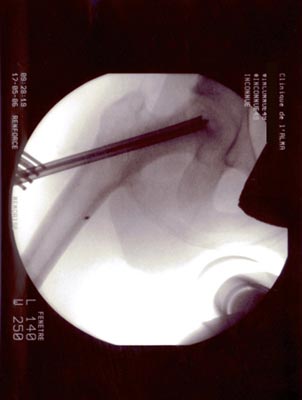

Technique opératoire Le trocart est introduit par voie pertrochantérienne et suit le trajet de la vis. Sa position dans la tête fémorale et dans la nécrose est repérée sous amplificateur de brillance de face et de profil. Une petite pince à séquestre retire les tissus fibreux et nécrosés circonférenciellement après repérage. Un lavage au sérum bétadiné complète le curetage. La moelle osseuse est prélevée (à l'aide du trocart de Mallarmé) sur la crète iliaque selon la technique classique. La moelle recueillie est d'autant plus riche en cellules souches qu'elle a été aspirée par petites fractions (2 ml). Ceci permet de réduire le degré de dilution par le sang périphérique. Elle est ensuite mélangée extemporanément avec le biomatériau. En général : 5 ml pour 5 cc de corail naturel. Sous contrôle Rx., le greffon est introduit à l'aide d'un trocart jusque dans la tête au niveau de la zone curetée : L'appui-contact avec 2 C.B est immédiat. Faut-il mettre en décharge avec traction et combien de temps ? Il ne sera possible de répondre à cette question que lorsque l'on saura avec précision la durée des phases de déminéralisation-reminéralisation du composite biomatériau-moelle osseuse aboutissant à de l'os néo- formé mécaniquement solide. C'est aux fondamentalistes de nous apporter la réponse.

OSTEONECROSE ASEPTIQUE de la H.D. Intervention en mai 2006